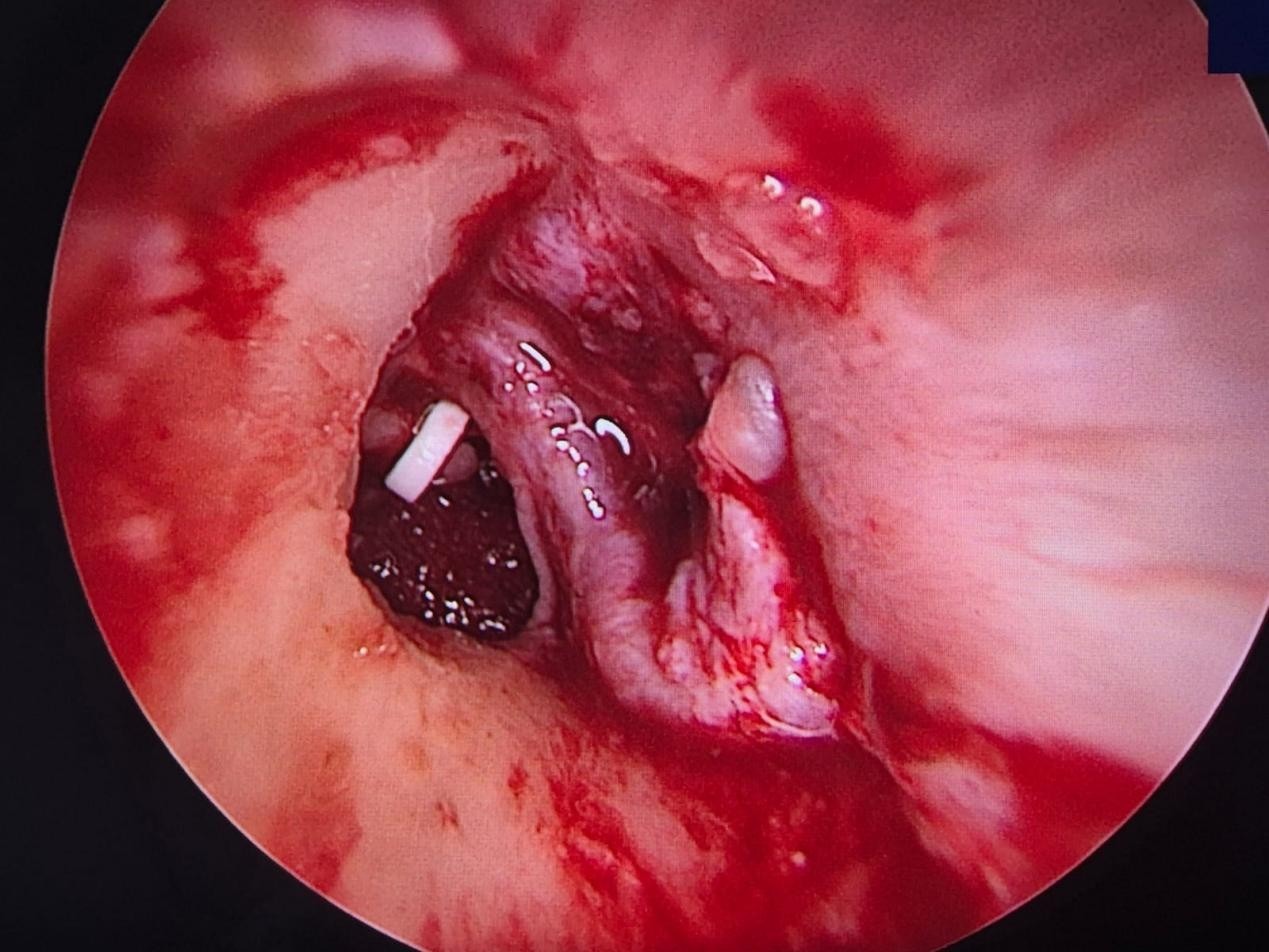

At Richardsons, we not only provide the best ENT treatment in India but also we take care that the surgery is generally done under local anesthesia, and the improvement in hearing can be appreciated immediately by the patient in the operating theatre. It is a daycare procedure, and the patient is discharged on the same day. The surgery involves no to very minimal pain. This surgery for otosclerosis is part of the Best ENT Treatment in India, offering minimal discomfort and fast recovery.

At Richardsons Face Hospital, we have an expert team of ENT surgeons and audiologists who can provide you with the utmost care and diagnosis with precision. The surgery, being performed completely endoscopic, provides a scarless surgery, quick recovery, and a permanent solution to improve your hearing. For the Best ENT Treatment in India, you can trust our skilled professionals. To know if you are the right candidate, kindly consult our expert team of doctors, and you can say “yes” to permanent effortless hearing and “no” to hearing aids.